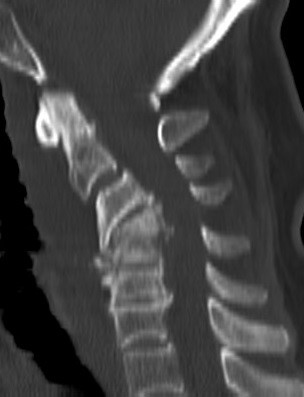

Ameliyat Öncesi